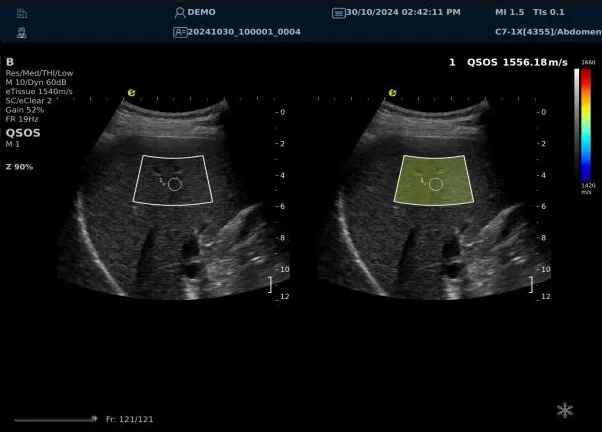

以上为应用声速定量成像技术检查肝脏的超声图像,图中在取样框内选择了三个测量区域,得出了各区域内的组织声速值以及声速衰减系数等结果。